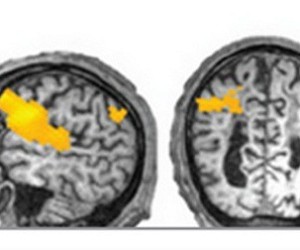

Учёные из института мозга поясняют, что многофункциональные центральные нейроны единовременно обеспечивают мышление и движение. Перегруженные спазмом нейроны не в состоянии заниматься своими функциями. Снять такие спазмы очень затруднительно.

Ботокс широко применяется в косметологии для борьбы с мимическими морщинами. А петербургские ученые доказали на деле, что препараты, основанные на ботулотоксине, после внутримышечного введения прекращают непрерывные импульсы, поступающие от конечностей находящихся в спазме. Таким образом, у нейронов головного мозга появляется возможность выполнять функции, связанные с мышлением.